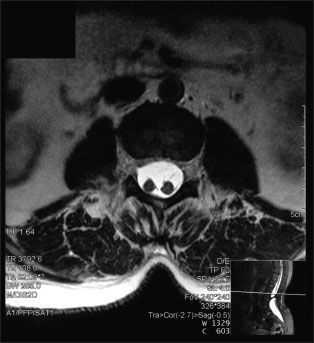

A 42-year-old woman had a “life-long” history of low back pain, without radiation, anesthesia, weakness, or incontinence. An MRI scan without contrast of the lumbar spine revealed a sagittal division of the spinal cord into 2 halves at the L2-3 level separated by a cartilaginous septum, or diastematomyelia, a rare congenital neural-tube defect.

Image courtesy of Millicent King Channell, DO, MA.